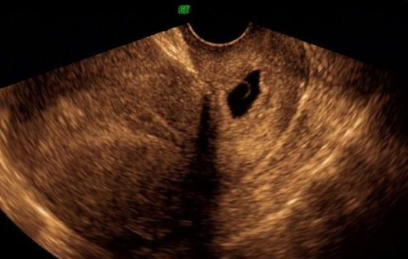

宮頸妊娠是一種異位妊娠,很多時(shí)候如果出現(xiàn)宮頸妊娠,對(duì)胎兒和母體本身的健康影響是很大的,那么宮頸妊娠藥物怎么治療 宮頸妊娠是大手術(shù)嗎。下面八寶網(wǎng)的小編就來介紹。